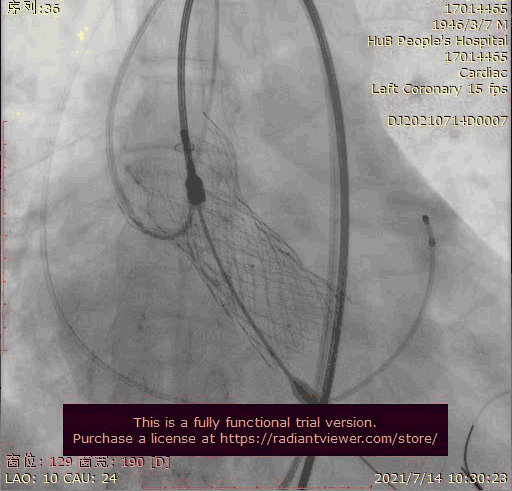

主动脉根部造影

输送器跨瓣

瓣膜稍高位释放

瓣膜位置稍深

使用venus-A plus回收后重新定位释放

瓣膜位置尚可

大结构瓣膜稳定性差,输送器使瓣膜跳到瓣上

奇思妙想使用射频消融大头压住支架至窦底

在大头压迫支架下释放第二个瓣膜

第二个支架完美释放固定第一个支架

术后基本无返流